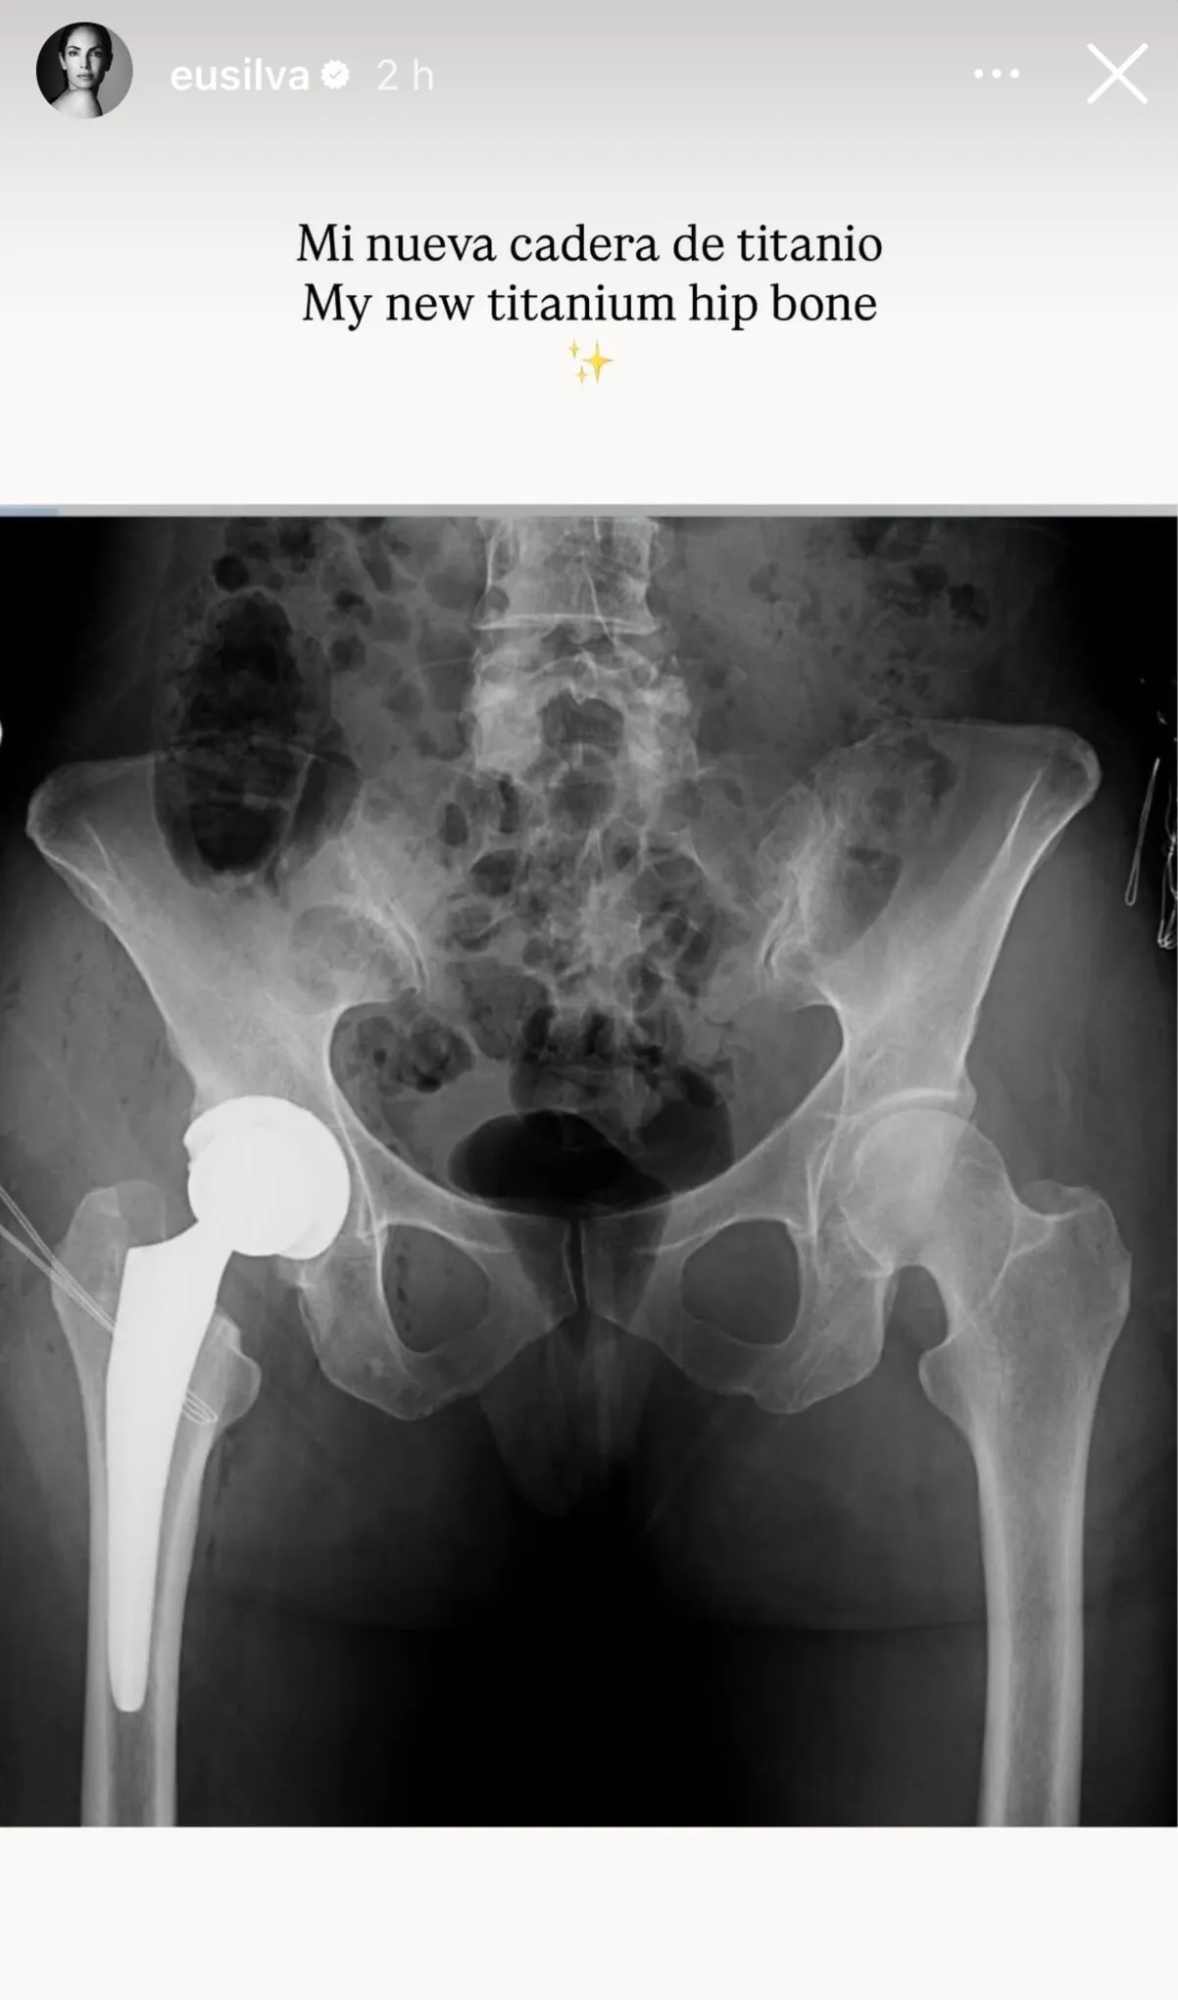

"Me han puesto una prótesis de titanio. Era necesario: el dolor ya no me permitía seguir con mi ritmo habitual", explicó, detallando el alcance de la operación que marcó un antes y un después en su día a día. La decisión no fue sencilla, pero fue la única salida para recuperar calidad de vida y volver a sentirse bien consigo misma.

Una radiografía de la cadera de Eugenia Silva compartida en sus redes sociales